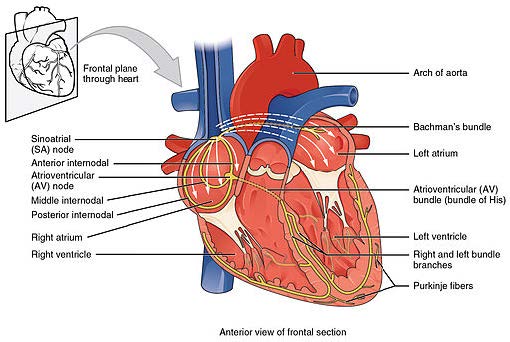

As previously stated, the heart is a mechanical pump driven by electricity. The heart has its own electrical impulses that travel along specialised pathways. The heart contracts and relaxes to pump blood around the body. The pumping action is possible because of electrical impulses that pass through the heart muscle (Marieb & Hoehn, 2010).

The SA node releases electrical stimuli at a regular rate, the rate is dictated by the needs of the body. Electrical stimulus passes through the myocardial cells of the atria creating a wave of contraction which spreads rapidly through both atria (Hatchett and Thompson, 2007). In other words, think of a wave of dominoes passing through the heart. The electrical stimulus from the SA node reaches the AV node and becomes delayed briefly. This allows the contracting atria have enough time to pump all the blood into the ventricles. Once the atria are empty, the valves between the atria and ventricles close. At this point the atria begin to refill and the electrical stimulus passes through the AV node and bundle of His into the bundle branches and Purkinje fibres (Hatchett and Thompson, 2007).

Then the ventricles contract – the right pumps blood to the lungs and the left pumps blood into the aorta. At this point the ventricles are empty, the atria full, the valves between them closed and the SA node is about to release another electrical stimulus.

There is another part to this process. The SA node and AV node contain only one stimulus. Therefore every time the nodes release a stimulus they must recharge before they can do it again. The SA node recharges while the atria refill. The AV node recharges when the ventricles are refilling (Hatchett and Thompson, 2007). Hence, there is no need for a pause in heart function. All of this in less than one third of a second. Pretty impressive!

The term used for the release (discharge) of an electrical stimulus is depolarisation and the term for recharging is repolarisation.